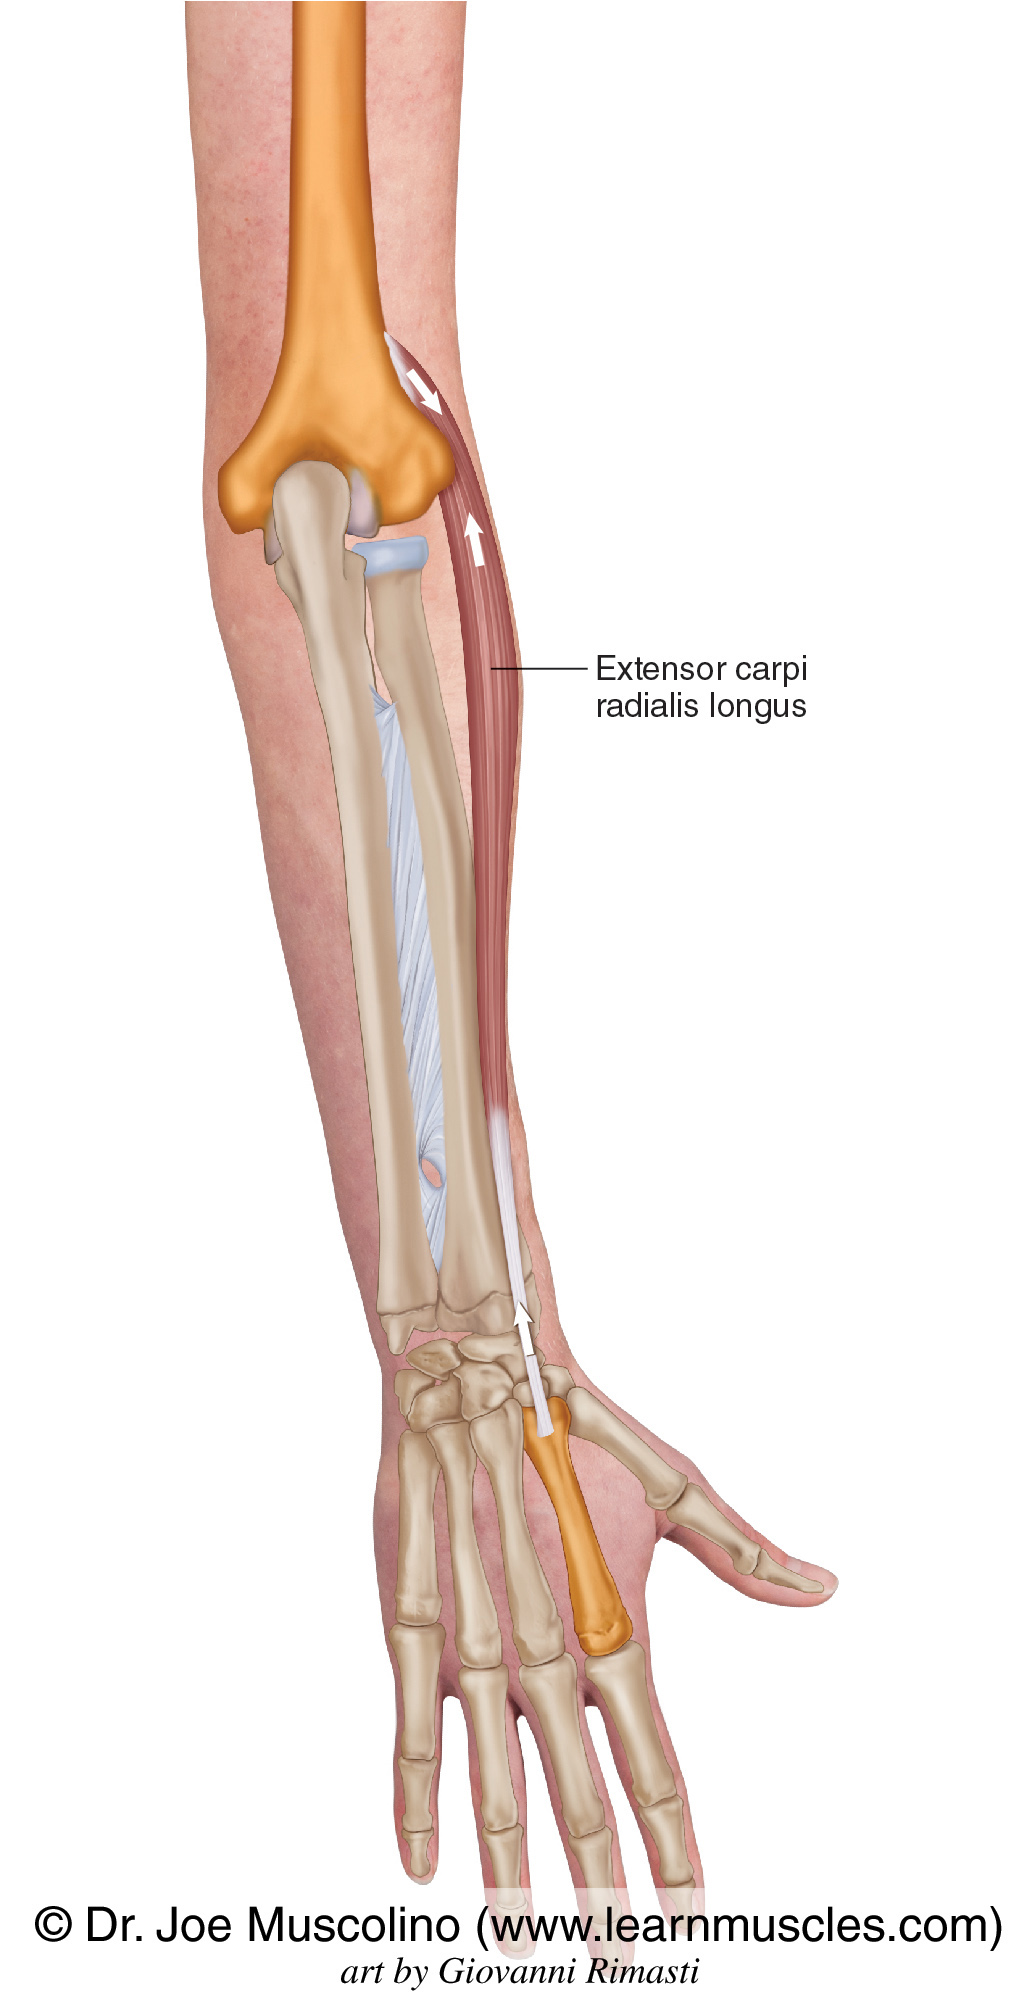

Анатомия и функции мышцы brachioradialis